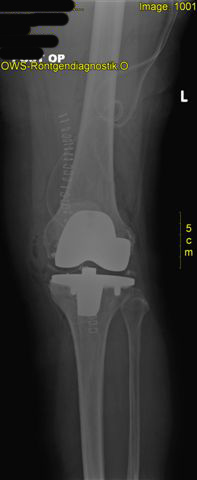

postoperativer Zustand mit liegender zementierter Knieprothese und gerade gestellter Beinachse